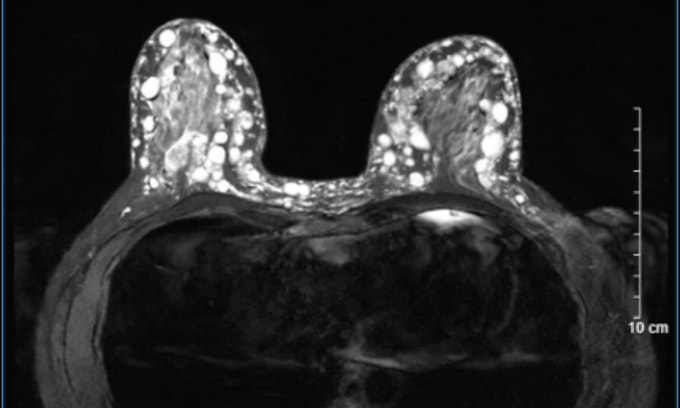

Bác sĩ Hoàng Hồng, Trưởng Khoa Phẫu thuật Tạo hình Thẩm mỹ, chẩn đoán bệnh nhân bị u hạt silicon (siliconoma) ở cả hai bên ngực. Các khối u này đã thâm nhiễm toàn bộ tuyến vú, lan rộng ra tổ chức mỡ dưới da, trung bì và sâu tới lớp cân cơ ngực lớn. Nếu trì hoãn, các u hạt sẽ tiếp tục phát triển, gây nguy cơ nhiễm trùng, hoại tử da vùng ngực.

Suốt hơn 7 giờ trong phòng mổ, các bác sĩ đã tỉ mỉ bóc tách, lấy bỏ toàn bộ các khối u hạt silicon, sau đó tạo hình lại vòng một trong cùng một lần phẫu thuật. Hiện sức khỏe bệnh nhân ổn định, hai bên ngực đã được tái tạo về hình dáng gần như bình thường.